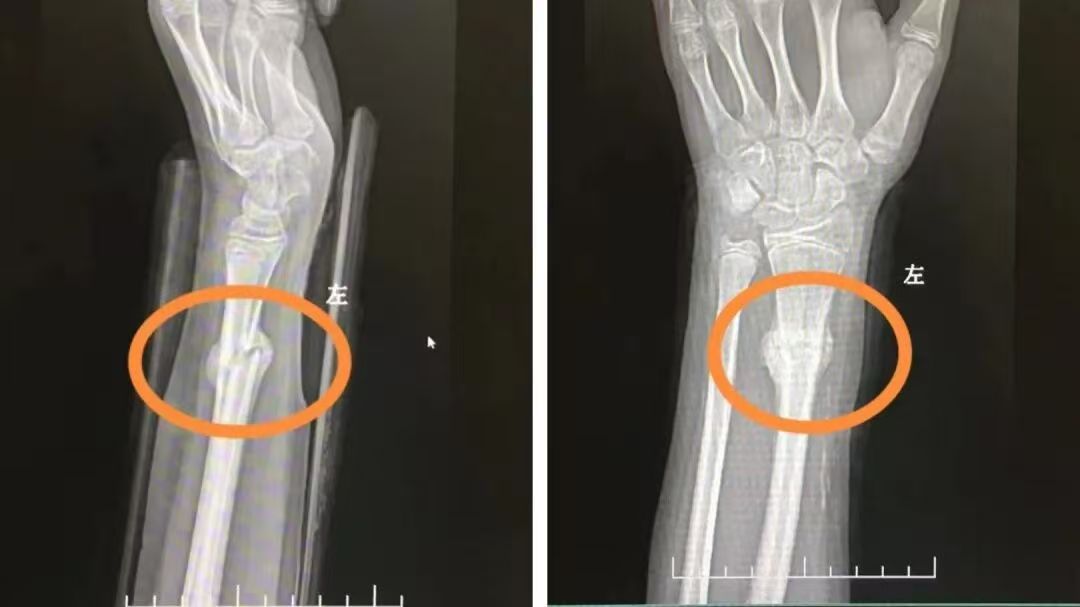

王女士(化名)在做家务时不慎摔倒,伤及右腕关节,出现局部肿胀、疼痛症状,活动受限,前往我院骨科就诊。经张靖主任详细查体及影像学诊断后,确诊为前臂骨骨折,为最大程度减少创伤、促进康复,张主任团队为其实施精准手法复位,快速矫正骨折移位,随后,再利用小夹板进行固定,拍片显示骨折对位完美,为后续愈合奠定良好基础。事后王女士不禁感叹:若非亲身经历,真不敢相信传统中医手法如此神奇。

张主任一边轻声安抚孩子,一边精准施力,手上感觉到一声轻微的“咔嗒”声,复位成功!随后,为孩子患肢进行了小夹板外固定,复查X光片显示,骨折端对位良好。儿童骨膜较厚,血运丰富,骨折愈合迅速,所以,绝大多数儿童骨折只需要手法复位或夹板外固定就可以达到治疗目的。